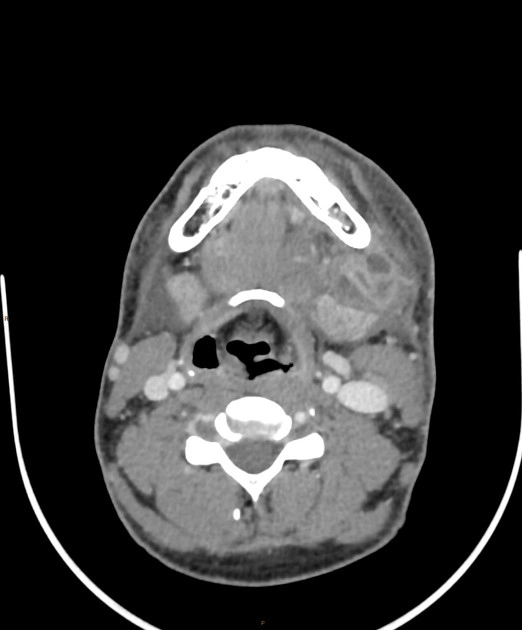

Hạch lao ở cổ (Tuberculous cervical lymphadenitis)